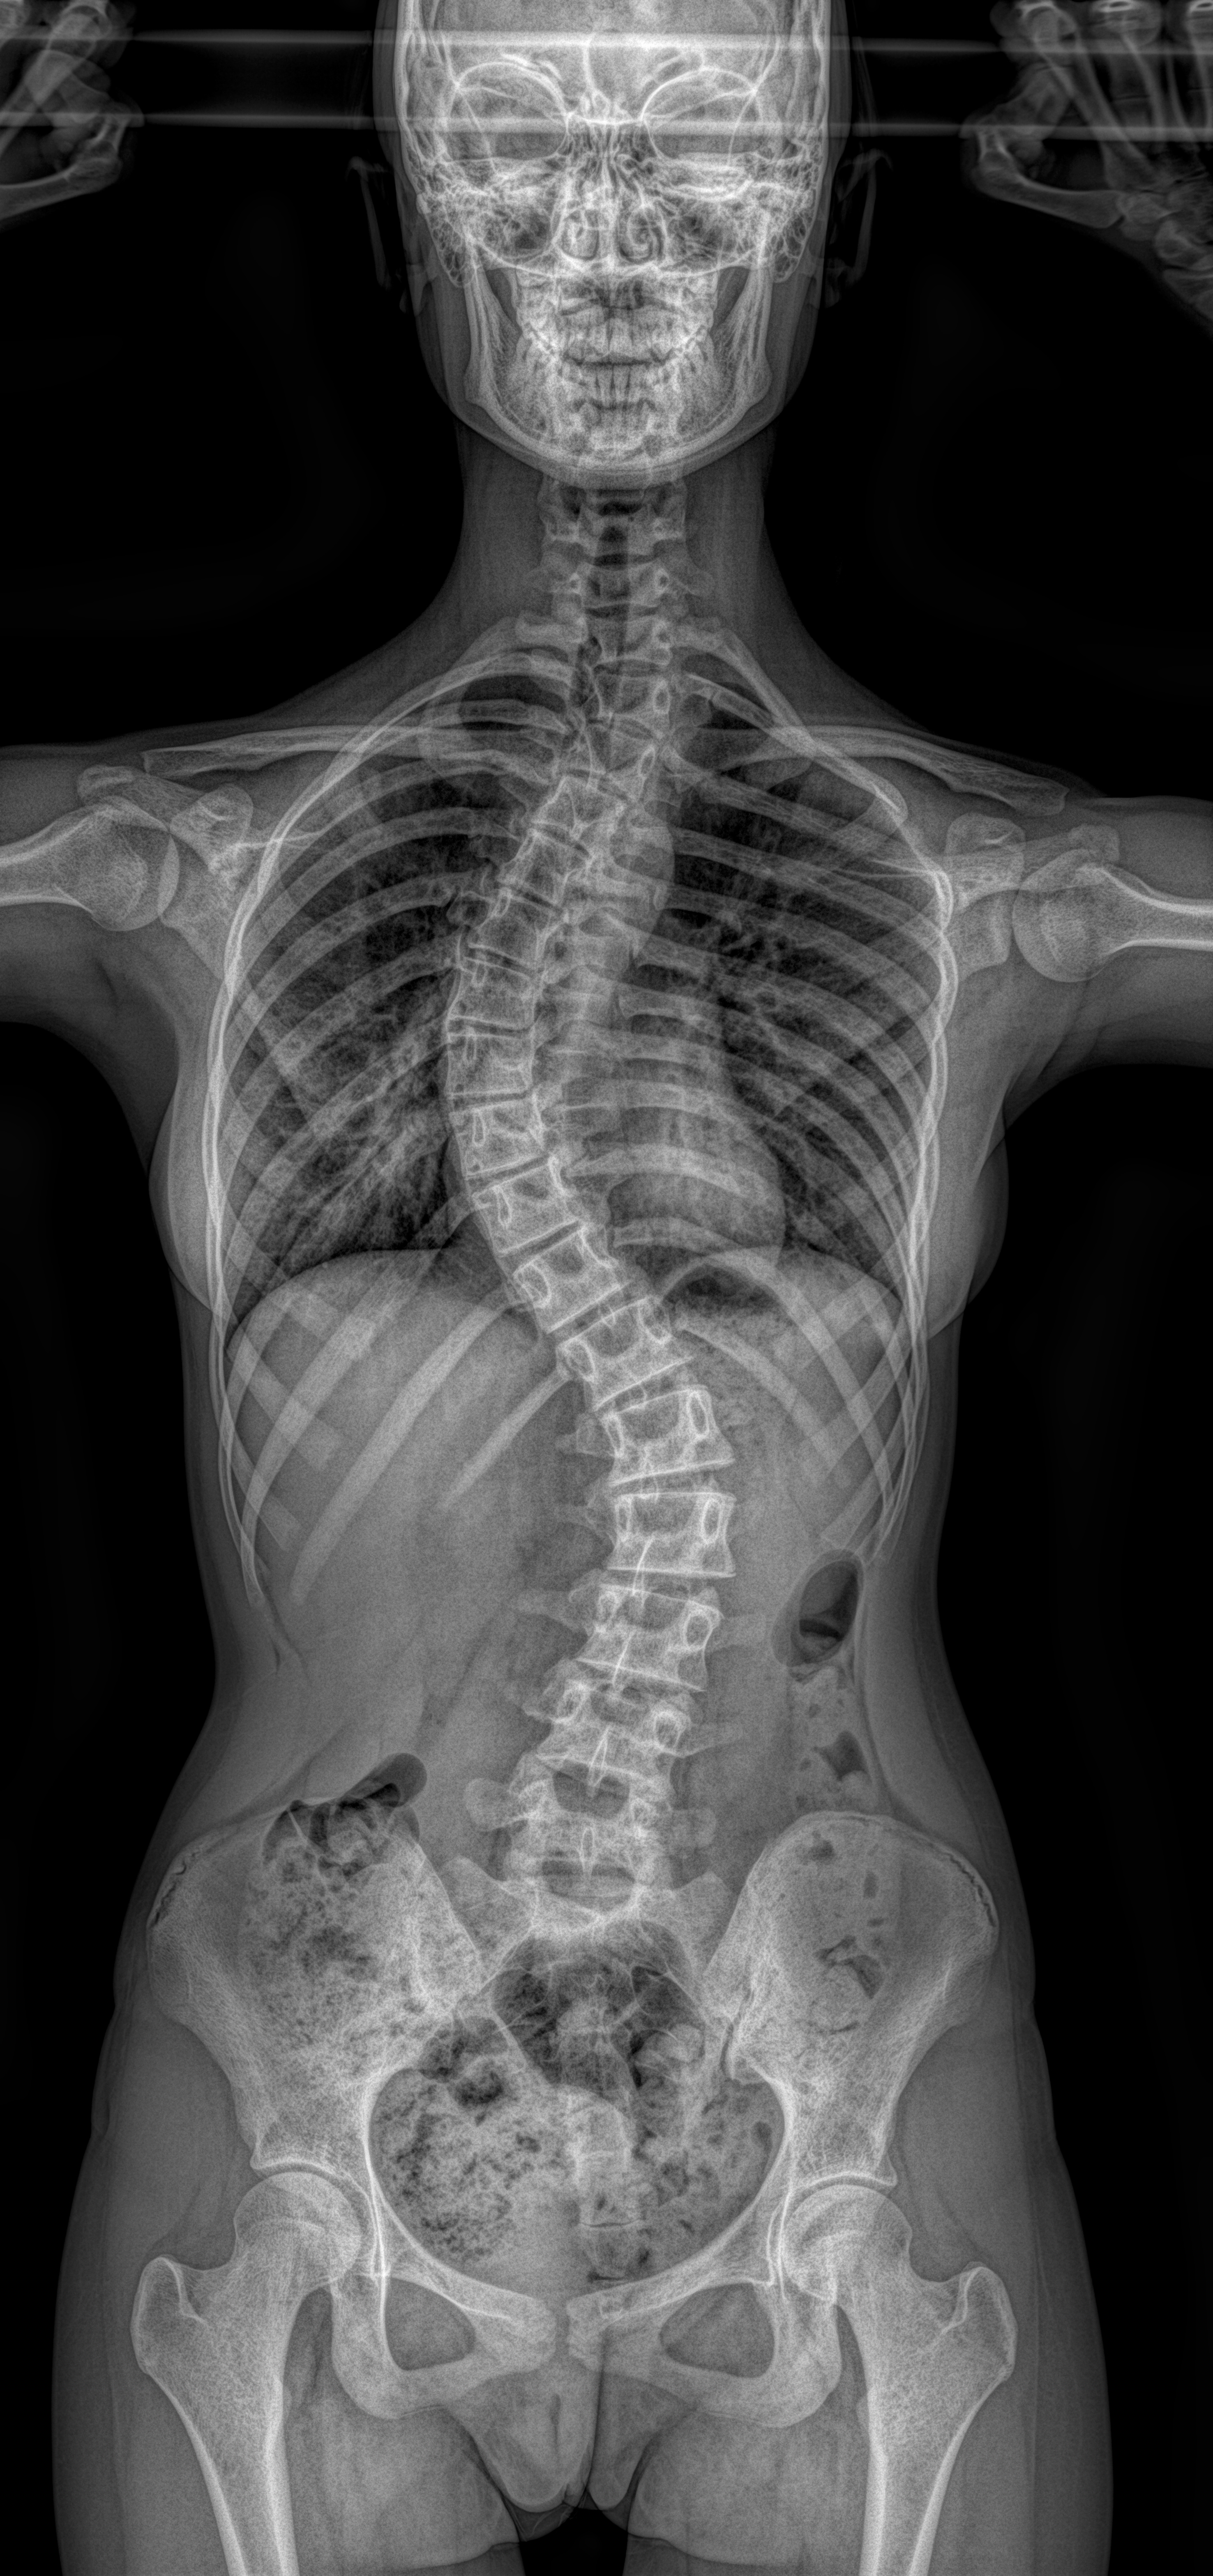

EOS skolyoz grafisi, omurga eğriliklerinin hassas ölçümlerle görüntülenmesine imkan tanır. Merkezimizdeki EOS cihazı, skolyoz takiplerinde güvenli ve tekrarlanabilir sonuçlar sağlar.